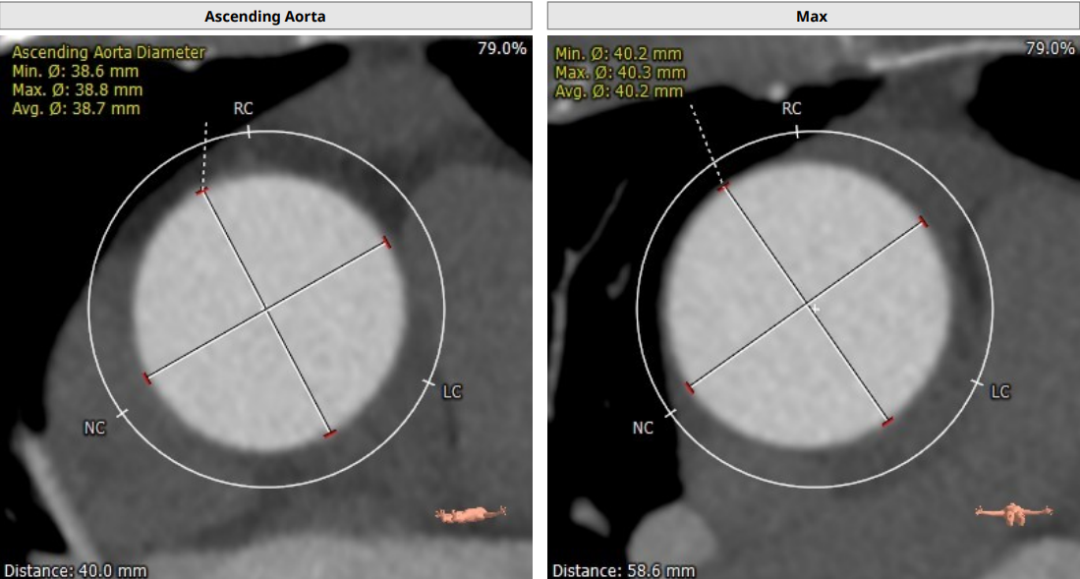

术前CT评估

Annulus Dimensions—25mm

LVOT—27.5mm

窦部:32.6*35.2*35mm

STJ—25.5mm

升主动脉存在明显增宽